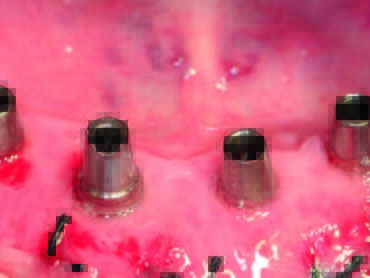

Die ATLANTIS Conus-Abutments, die zugleich als industriell gefräste Primärteile dienen sollten, sowie der zugehörige Einbringschlüssel wurden versandt. Die vier Conus-Abutments wurden unter Zuhilfenahme des Einbringschlüssels inseriert (Abb. 18). Es zeigte sich eine ausgezeichnete Parallelität. Danach wurden die Abutments implantatspezifisch (Astra Tech OsseoSpeed Abb. 14: Die vier verschiedenen Implantate in situ mit ihren jeweiligen Verschlusskappen. Abb. 15: Gingiva oder Sulkusformer. Abb. 16: Gingiva- oder Sulkusformer in situ. EV mit 25 Ncm, Straumann mit 35 Ncm, ANKYLOS mit 15 Ncm, Xive mit 24 Ncm) definitiv angezogen (Abb. 19). Abschließend erfolgte eine abschließende radiologische Kontrolle (Abb. 20). Die ANKYLOS Konuskappe Degulor für SynCone 5° wurden dem Patienten mitgegeben. Der überweisende Zahnarzt war in die Planung und Gestaltung der Endversorgung von Anfang an mit Abteilungsleieinbezogen. Seitens der Autoren wurde die Einpolymerisierung der Konuskappen (Abb. 20) in die vorhandene Prothese allein aus wirtschaftlichen Erwägungen angeraten.